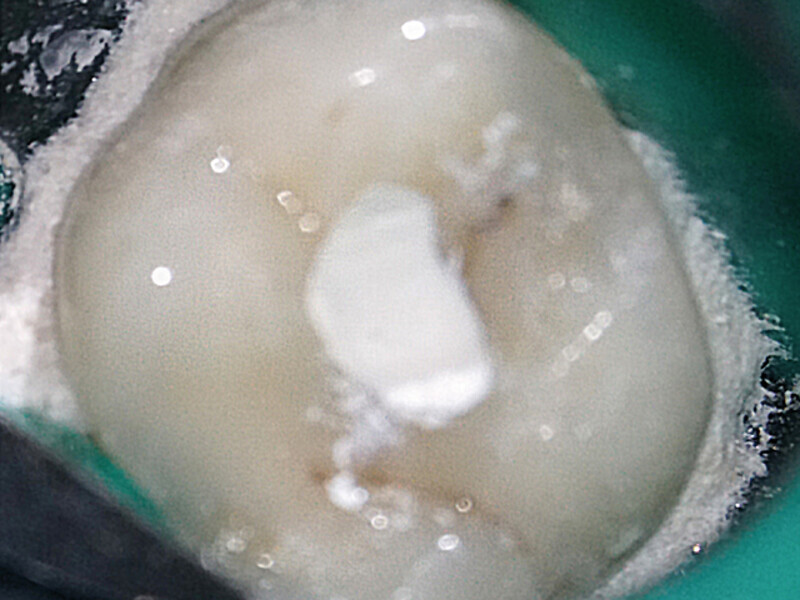

Endodontické ošetření – případová studie